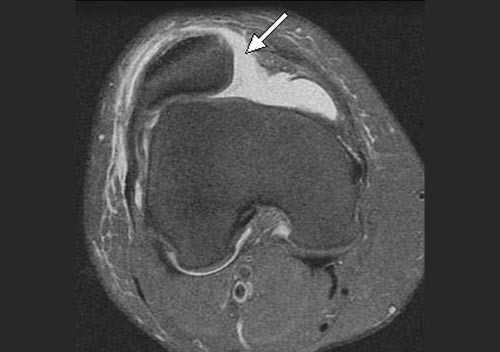

- МРТ (магнитно-резонансная томография) — единственный метод диагностики состояния мягкотканных структур коленного сустава: мышц, сухожилий и связок. Врач оценивает состояние бугристости, отёк связки надколенника, повреждение менисков, отсутствие или наличие свободной жидкости в полости коленного сустава. МРТ назначают при отёке коленного сустава и боли в спокойном состоянии [16] . Этот способ позволяет исключить внутренние повреждения коленного сустава (повреждение крестообразных связок, менисков, коллатеральных связок коленного сустава, изменения тела Гоффа).

В большинстве случаев врач-травматолог легко диагностирует привычный вывих надколенника. Для этого проводится серия нагрузочных тестов, во время которых пациент демонстрирует страх получения повторного вывиха. Окончательный диагноз ставится после проведения магнитно-резонансной томографии (МРТ) коленного сустава. Как правило, исследование обнаруживает признаки повреждения медиальной пателло-феморальной связки, состояние подвывиха надколенника и признаки травматических повреждений хрящевого покрова.